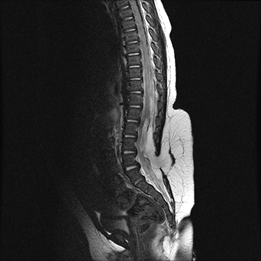

출생 후 피부 이상으로 병원을 찾게 되는 경우가 가장 흔하다. 척추 초음파로 이상여부를 확인할 수 있으며 정확한 진단은 척추에 대한 자기공명영상(MRI)의 촬영을 통해 실제 척추관 내에 지방이 존재하며 척수의 끝 부분인 척수원뿔이, 척수가 결박되어 있어 정상보다 아래쪽에 위치하는 소견 등을 확인하여 내리게 된다. 확진을 위한 자기공명영상 외에 현재 신경 증상에 대한 평가를 하게 된다. 우선 배뇨 기능 평가를 위해 요류 역학검사 및 방광역류에 대한 검사를 한다. 또한 하지의 근전도 검사를 시행하게 되고, 척수에 대한 초음파 검사를 하기도 한다.

지방 척수 수막류 MRI